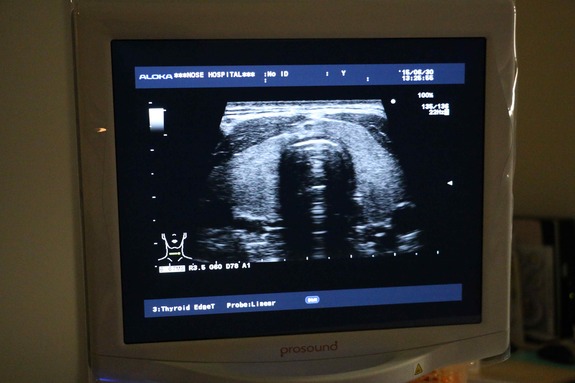

昨日、こどもしんじが福島で甲状腺エコー検査を撮影するために関西の某病院で撮影を行いました。モノクロの画面ではのうほうと、血管の違いがわからない場合もあるので、最新のカラーも映せる機械で確認をするのだそうです。

のうほう(水がはいったもの)はそのまま黒く、欠陥部分はカラーでピンクに見えます。健康な人でものうほうがある人はかなりいる。ただ、若い人の場合、状況が急変する場合があり、継続的な検診が必要だとのこと。

(福島県立医科大学の診断結果の送付は単なるAとかA2とかしか書いていないのですが、エコーの画像やのうほうの数、サイズなどを定期的にみていく必要があります)

甲状腺機能は人体にとってとても重要です。ホルモンバランスを整えたり、成長に必要なホルモンを出したり。一番右の画像は、橋本病と診断された方の甲状腺です。素人でもわかるおかしな影が見えます。甲状腺のサイズが大きくなったり、中に異常がみられたりすると橋本病やバセドー病と診断されます。目が大きくなるなどの症状が見られます。